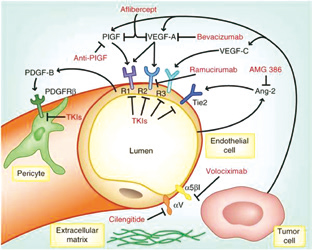

美国纪念斯隆凯特琳癌症中心Lee等报告,在免疫治疗(IO)失败的转移性肾细胞癌(mRCC)患者中,约2/3的患者经VEGF抑制联合免疫检查点抑制剂治疗后有缓解。(2019 IKCS)Lenvatin…

美国加州大学的Lara和MD Anderson癌症中心的Campbell就非透明细胞型肾细胞癌(nccRCC)目前的治疗策略进行了激烈辩论。(国际肾癌研讨会IKCS 2019)ICI的优势Lara支持将免疫检…

Atezolizumab联合贝伐珠单抗在RCC中的应用

美国Dana-Farber癌症研究所McGregor等报告,Atezolizumab联合贝伐珠单抗治疗不同组织学类型(variant histology)晚期肾细胞癌(RCC)、或治疗任何组织肉瘤样分化成分≥20%的RC…